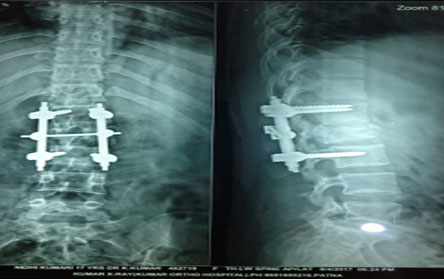

The Center of Orthopedics KUMAR ORTHO HOSPITAL ,Patna, offers the entire spectrum of modern orthopedic management, which is effective, patient - friendly & result oriented. In a nutshell, it is one stop treatment for all orthopedic ailments and fractures with emphasis on avoidance of complications, rapid mobilization, decreased period of confinement and an early return to normalcy.

Trauma surgery:

Trauma surgery is a surgical specialty that utilizes both operative and non-operative management to treat traumatic injuries.